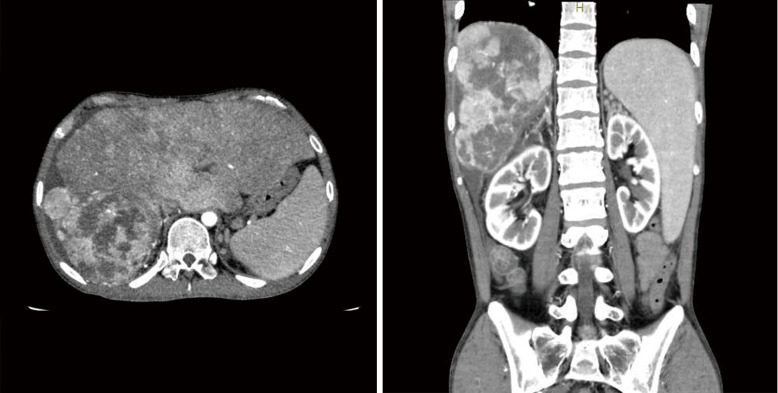

This paper presents case studies of adult patients with congenital heart disease (CHD) who developed cancer and also discusses relevant epidemiological studies, risk factors, and reports on early detection. Herein, we describe three cases: a 63-year-old man with an atrial septal defect and multiple myeloma; a 48-year-old man with tetralogy of Fallot and colorectal cancer; and a 25-year-old man with Fontan circulation and hepatocellular carcinoma (HCC). Previous studies have found that the incidence of cancer in adult patients with CHD is higher than that in the general population. The management of adult patients with CHD complicated by cancer requires careful attention because cancer treatment alone can affect the survival prognosis and quality of life, as well as the pathophysiology and treatment of underlying heart disease. Apart from known risk factors in the non-CHD population, specific risk factors have been reported, such as genetic abnormalities, low-dose ionizing radiation exposure, early thymectomy, Fontan-associated liver disease, and hypoxia. Encouraging patients to participate in cancer screening and avoid known risk factors is essential in daily practice for the early diagnosis and prevention of cancer. It is also important to be vigilant for initial signs that are indicative of cancer as well as avoidable risk factors.

Abstract Image